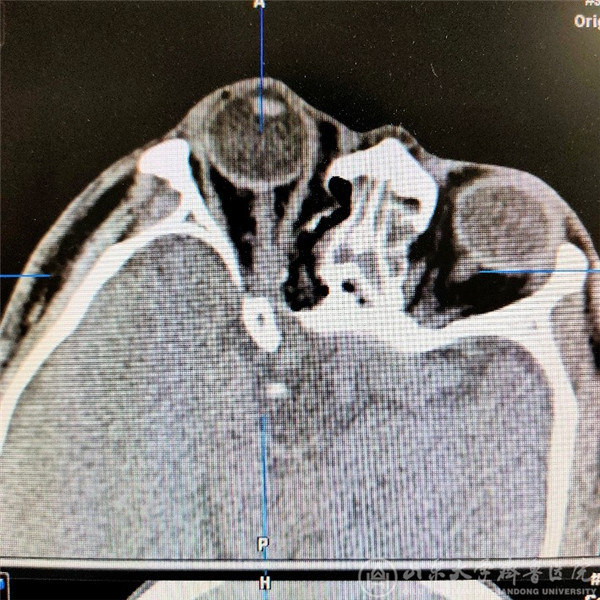

患者中年男性,3个月前无明显诱因出现右眼视物模糊伴视野受限。在多家绿帽社就诊,确认为右眼眶内肿瘤,病变位于右侧眶尖部,压迫视神经,手术风险较大。患者及家属仔细考虑后来我院就诊。徐淑军教授及陈腾教授经过反复观察患者眼眶磁共振及CT后,鉴于病变位于右侧眶尖部内上象限,决定对该患者进行神经内镜下经鼻蝶入路的眼眶手术。该手术尚未在我院独立完成过,手术涉及眼科、耳鼻喉科、神经科等多个学科的解剖及临床知识,难度较大,风险较高。徐淑军教授结合神经导航系统,将患者的影像学资料汇总入神经导航软件,模拟出手术的路径和术中需要注意避免损伤的重要血管及神经。决定采取神经内镜下眶内肿瘤切除术,并在功能内镜组成员李超副主任医师、杨宁主治医师协助下完成。手术过程如下,患者全麻下取仰卧位,收敛双侧鼻腔粘膜,经右鼻腔置入0度神经内镜,去除右侧中鼻甲扩大手术野,打开右侧钩突、筛泡后,进入蝶窦及筛窦内,经解剖标志确认右侧眶内侧壁、视神经管及颈动脉隆起。使用高速磨钻去掉眶内侧壁骨质纸样板、视神经管骨性结构,充分显露右侧视神经管内段及眶内段走行,剪开眶筋膜,确认右侧内直肌,在其内上方可见肿瘤,与周边组织分离后,完整切除肿瘤。使用左侧鼻中隔粘膜瓣进行眶壁及颅底的修补,预防脑脊液鼻漏。术后第一天患者右眼视力明显改善,由术前4.2恢复至4.6,视野明显扩大,手术效果满意。

(术后可见右眼眶内肿瘤完整切除,视神经无受压,眶内正常结构未破坏)